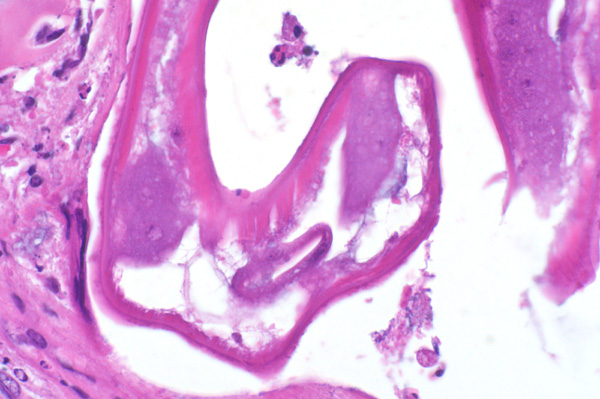

The nematode has a thick (5-8µm) smooth cuticle, polymyarian-coelomyarian musculature, lateral chords (C), and a pseudocoelom containing an intestine (I) lined by few multinucleate cells.